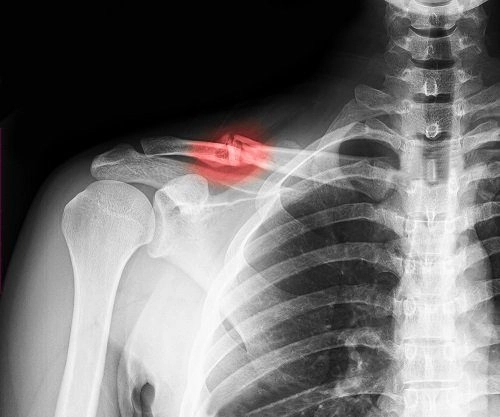

Trường hợp xương đòn bị gãy làm đôi và chệch khỏi vị trí ban đầu thì cần phẫu thuật

- Xương đòn chọc ra da, mảnh xương gãy chọc vào đỉnh phổi gây biến chứng ở phổi, gãy hai xương đòn (vì sợ ảnh hưởng đến hô hấp do bệnh nhân thở sẽ bị đau)

- Gãy xương đòn di lệch quá nhiều so với vị trí ban đầu

Hoặc khi xương đòn chồi lên khỏi bề mặt da

Phẫu thuật gãy xương đòn trong trường hợp này rất cần thiết nhằm kết nối các phần xương bị vỡ và gãy vụn lại với nhau, đồng thời đưa vị trí xương đòn bị gay về vị trí ban đầu.